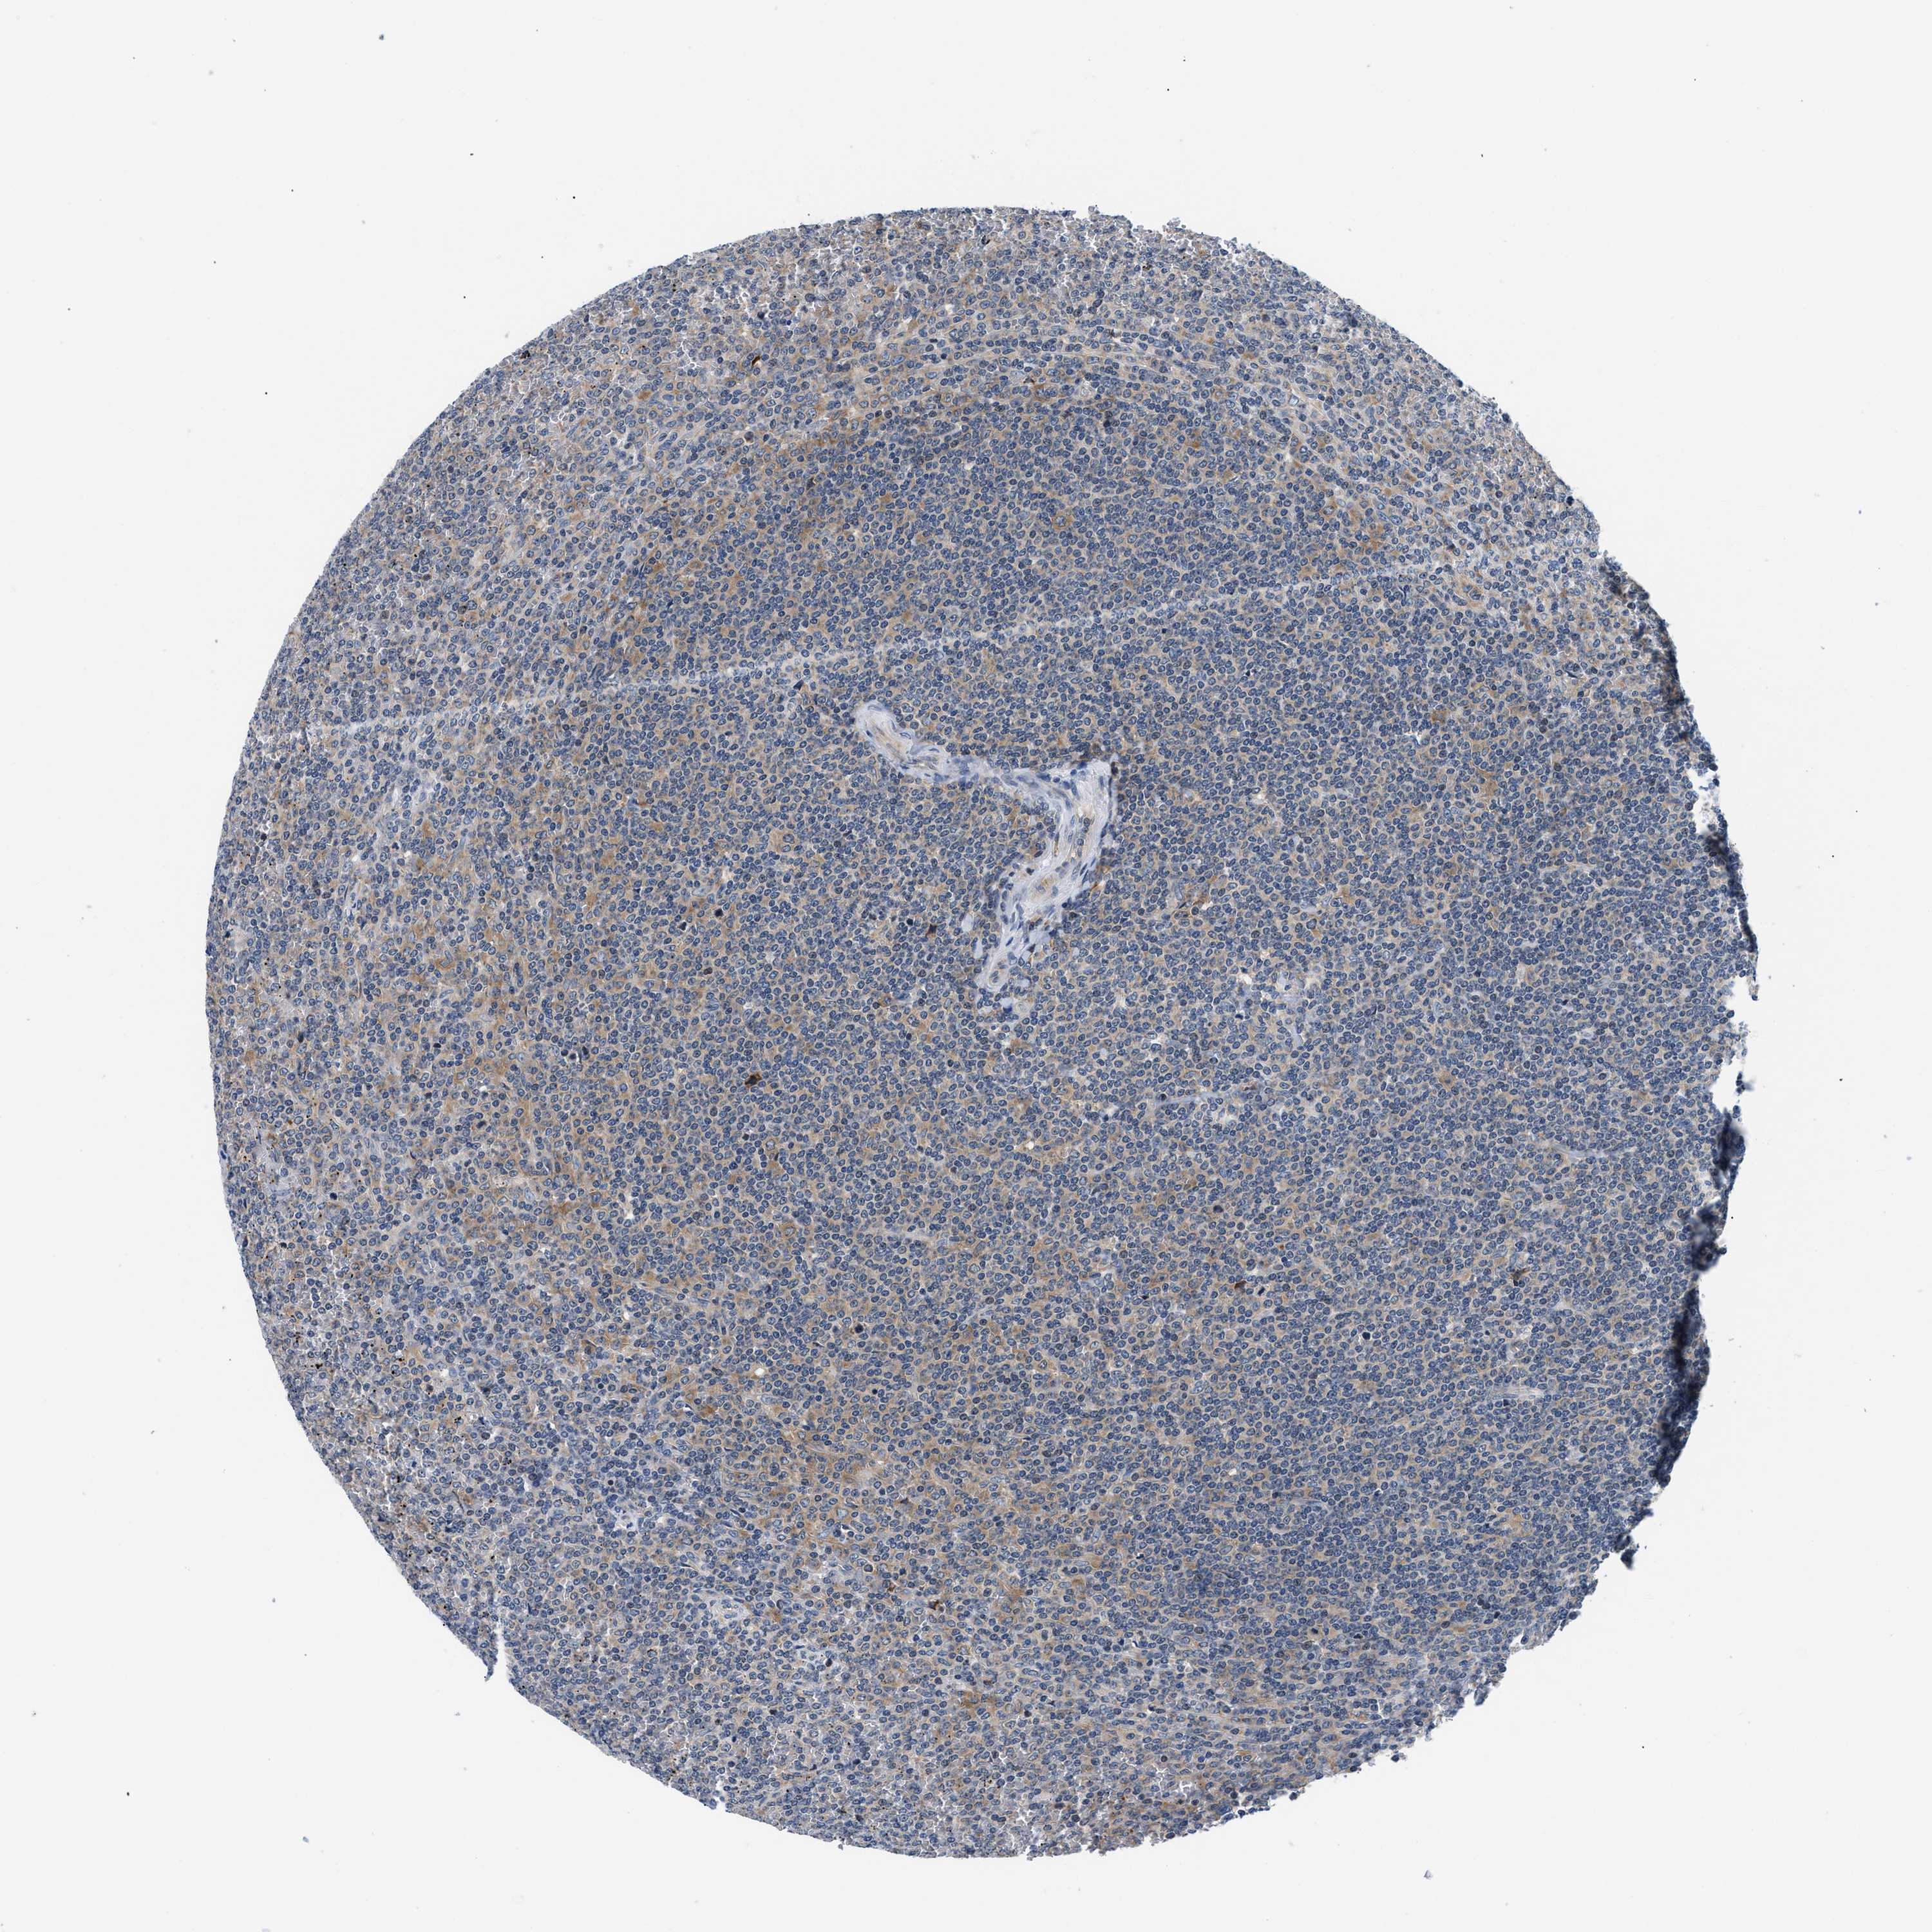

CANCER LYMPHOMA Show tissue menu

LYMPHOMA - Protein expressioni

A mouse-over function shows sample information and annotation data. Click on an image to view it in a full screen mode. Samples can be filtered based on level of antibody staining by selecting one or several of the following categories: high, medium, low and not detected. The assay and annotation is described here.

Antibody stainingi

Antibody staining in the annotated cell types in the current human tissue is reported as not detected, low, medium, or high, based on conventional immunohistochemistry profiling in selected tissues. This score is based on the combination of the staining intensity and fraction of stained cells.

Each image is clickable and will lead to virtual microscopy that enables deeper exploration of all samples and also displays staining intensity scores, fraction scores and subcellular localization as well as patient and tissue information for each sample.

Antibody HPA015788

Antibody CAB025983

Staining

High

Medium

Low

Not detected

Intensity

Strong

Moderate

Weak

Negative

Quantity

>75%

75%-25%

<25%

None

Location

Nuclear

Cytoplasmic/membranous

Cytoplasmic/membranous,nuclear

Hodgkin's disease, NOS

Malignant lymphoma, non-Hodgkin's type, High grade

Malignant lymphoma, non-Hodgkin's type, Low grade